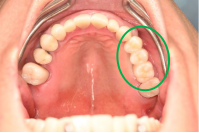

Before

※赤丸は、歯根が破折していたため抜歯しました

※黄色丸は、2006年10月に埋入したインプラント

After

※緑丸は、今回埋入したインプラント